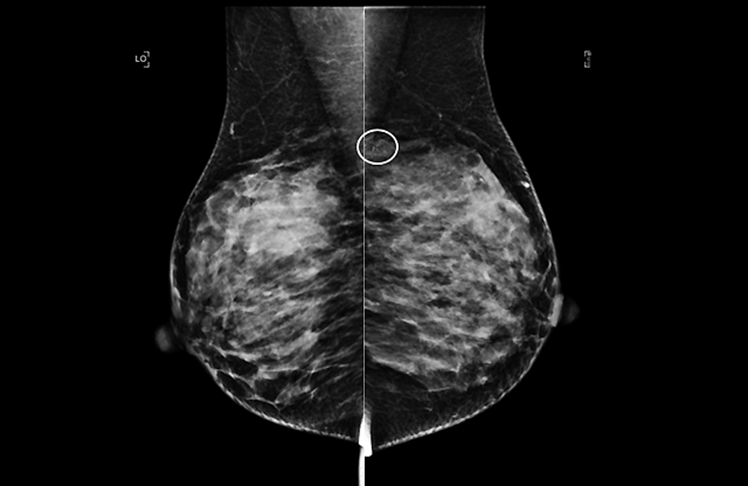

From March to September 2020, breast biopsies and detected cancers at U.S. Breast Cancer Surveillance Consortium facilities dropped sharply, compared with the same span a year earlier: Biopsies declined by 23% and detected cancers by 24%.

Newly published research attributes those downturns mostly to the postponement of routine screening mammograms as the COVID-19 pandemic took hold.